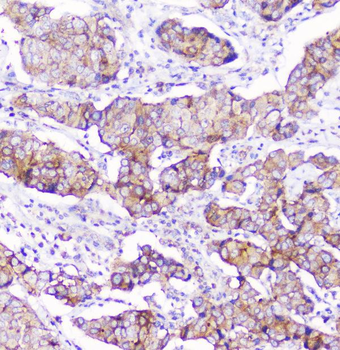

10 μg, 100 μg - Cubilin antibody [orb4997]Featured

ICC, IF, IHC-P, WB

Human, Mouse, Porcine, Rat

Rabbit

Polyclonal

Unconjugated